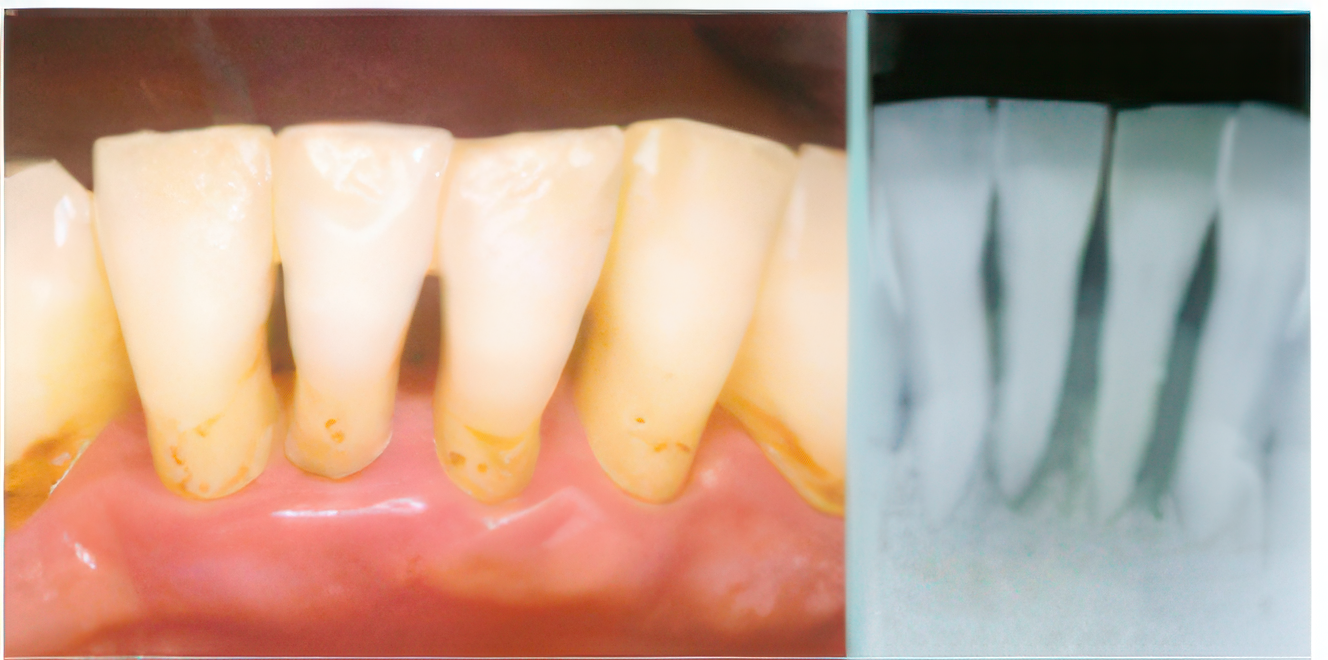

中等度歯周炎の症例

歯周病は、虫歯と同様に適切なブラッシングが行われていないことから、プラーク中の細菌が原因で引き起こされる病気です。日本では成人の6~7割以上が罹患しているといわれ、放置すると歯を失う危険性があります。健康な歯周組織では、歯と歯茎の境目である歯内溝の深さは1~2㎜ですが、歯周病病原菌の影響や噛み合わせの不調和が重なると歯周ポケットが深くなり、歯を支える骨(歯槽骨)が痛みなく失われていきます。

治療としては、歯周ポケット内の歯の表面を徹底的に清掃し、健康ではない不良肉芽を取り除き、歯と歯肉の新しい面を露出させることで治癒を促します。この治療により、歯周組織の回復を目指します。また、歯周病を防ぐためには、患者様それぞれに適したブラッシング法を身につけていただくことが重要です。個々の歯の形状やプラークがたまりやすい部位が異なるため、染め出しによるプラークの可視化を用いたブラッシング指導を行い、効果的なセルフケアをサポートしています。